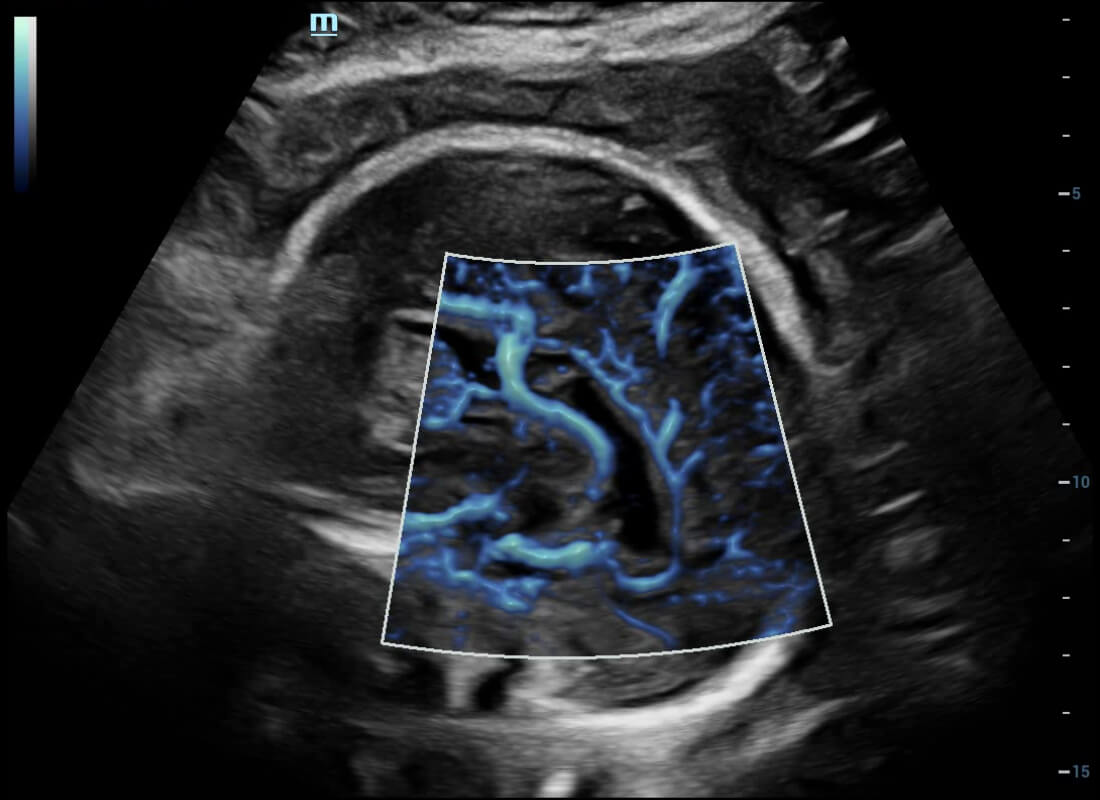

Central nervous system (CNS) malformations are one of the most common congenital abnormalities. Unfortunately, due to imaging limitations such as poor fetal position, acoustic shadowing, and operatorsŌĆÖ poor scanning skills, the MSP is particularly difficult to find in a 2D ultrasound. In this case, a faster and more user-friendly method, which automatically displays the standard planes together with the required measurements in a fetal CNS examination, could significantly boost both the quality and efficiency of clinical diagnoses.?NuewaŌĆÖs intelligent solution of fetal brain can realize automatic acquisition of brain volume data based on intelligent recognition of CNS application scenarios, intelligent generation of four fetal brain standard planes including MSP, automatic measurement of CNS biological items and automatic evaluation of fetal brain volume. More importantly, Nuewa's leading color Doppler technology can provide a clear and sensitive dynamic display of blood flow in the tiny vessels.